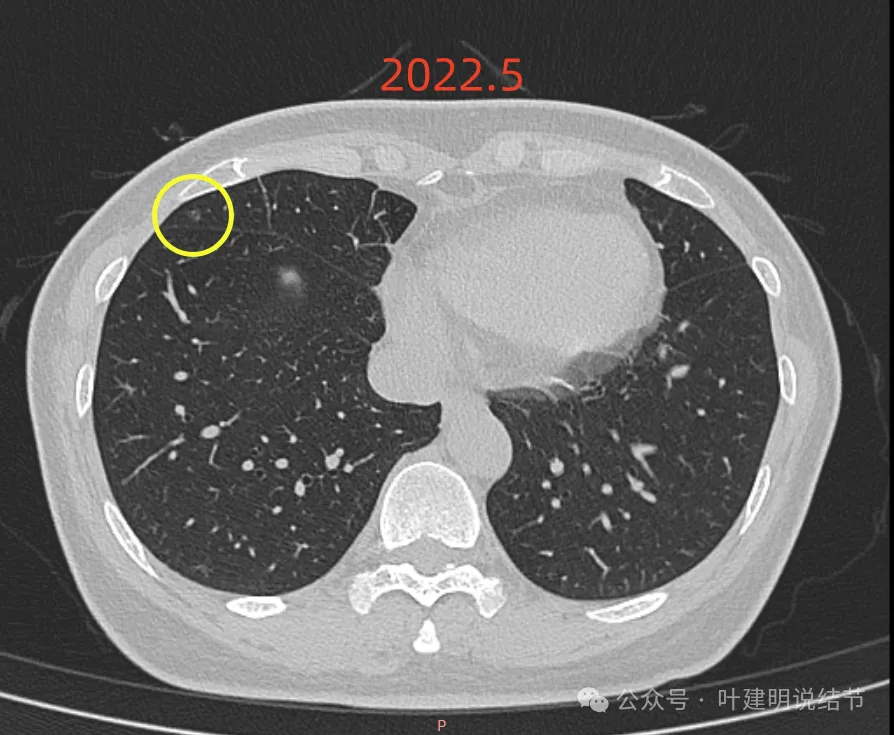

再看2022年5月时的影像:

这时B医院医生主张手术时的情况:

三处病灶均仍在,间隔3个月显然说不上明显进展或变化。这时候问诊我,我对比后认为风险仍低,能再随访,结友停掉了本已经预约的手术。